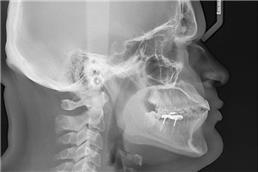

זקוקים לצילומי שיניים וחשוב לכם לקבל מענה מקצועי, אמין, מהיר ויעיל? מכון פנורמי סנטר לשירותכם! כמכון רנטגן מוביל בתחומו, אנו מבצעים צילומי שיניים ולסתות לרבות צילומי CT ואמונים על מתן שירות מקצועי, אדיב, אישי ויעיל לכל לקוח ולקוח. לנוחיותכם, אנו מספקים את מיטב שירותינו באמצעות שלושה סניפים לרבות סניף ברמת ישי, סניף ביוקנעם וסניף במגדל העמק ונשמח לעמוד גם לשירותכם לשביעות רצונכם המלאה!